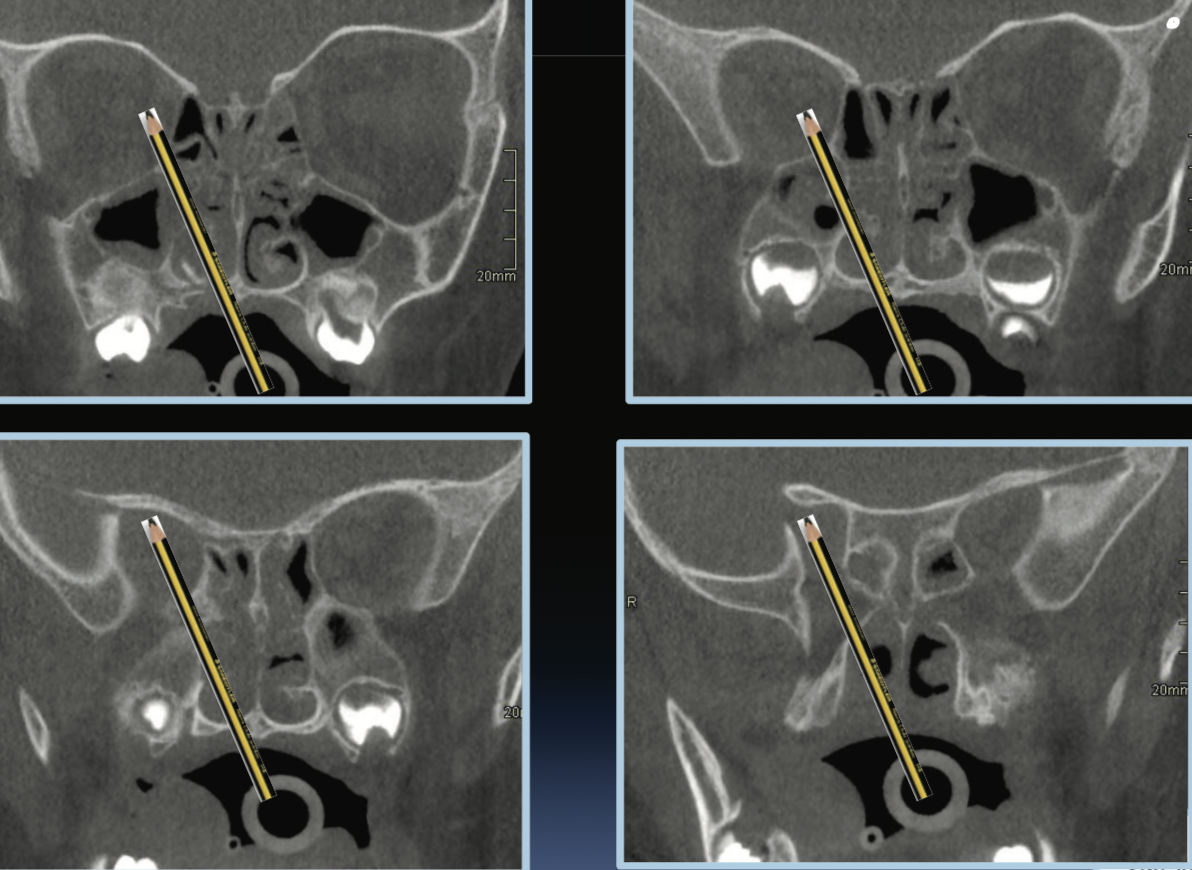

ORBITAL FRACTURES?

Orbital Apex fragments can lead to optic nerve damage

.